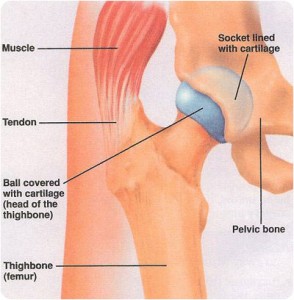

- Arthritis – Painful inflammation and stiffness of the joint and breakdown of the cartilage that normally cushions your hip bones

- Bursitis – Inflammation of the bursa (a fluid-filled sac or sac-like cavity found in places in tissues where friction would otherwise occur) that is usually due to repetitive activities that overwork or irritate the hip-joint.

- Tendonitis – Inflammation of the tendons in the hip-joint, also caused by overworking and repetitive use.

- Fracture – A crack or break in the hip-joint. Most fractures require surgery to repair when the bone moves and can cause more damage to the joint. With almost all of these conditions weight has an effect, the more you carry the more the joint has to carry.

This tension and inflammation can also cause a tightening of the muscles in your low back and behind. The inflammation in the joint can be alleviated with an over-the-counter anti-inflammatory medication (such as ibuprofen) or homeopathic remedies (such as Arnica Montana), when used in combination with rest and massage.

So what can massage do to help alleviate the pain in your hips? Massage opens and releases the lactic acid that accumulates in the tissue when it is less mobile. It also brings circulation to the joint, to help move out the extra fluid that builds up in the inflammatory process.

The idea is that as the pain grows, so does our tendency to favor a painful joint, throwing the rest of our body off center. By mobilizing the entire joint, you create a new pathway and release the accumulated fluid, allowing for much easier movement.

As we practiced this new technique on the hips, we were surprised to find that, not only, were the gluteal muscles sore and tender, but so were the quadriceps and hamstrings, as well as the groin muscles.

By applying gentle but firm pressure to the ligaments and muscles of an extended joint, it both releases the muscles and opens up the joint. It’s amazing just how much better you feel after just one treatment, and we’re continuing to treat Esther’s hips to return them to full mobility.